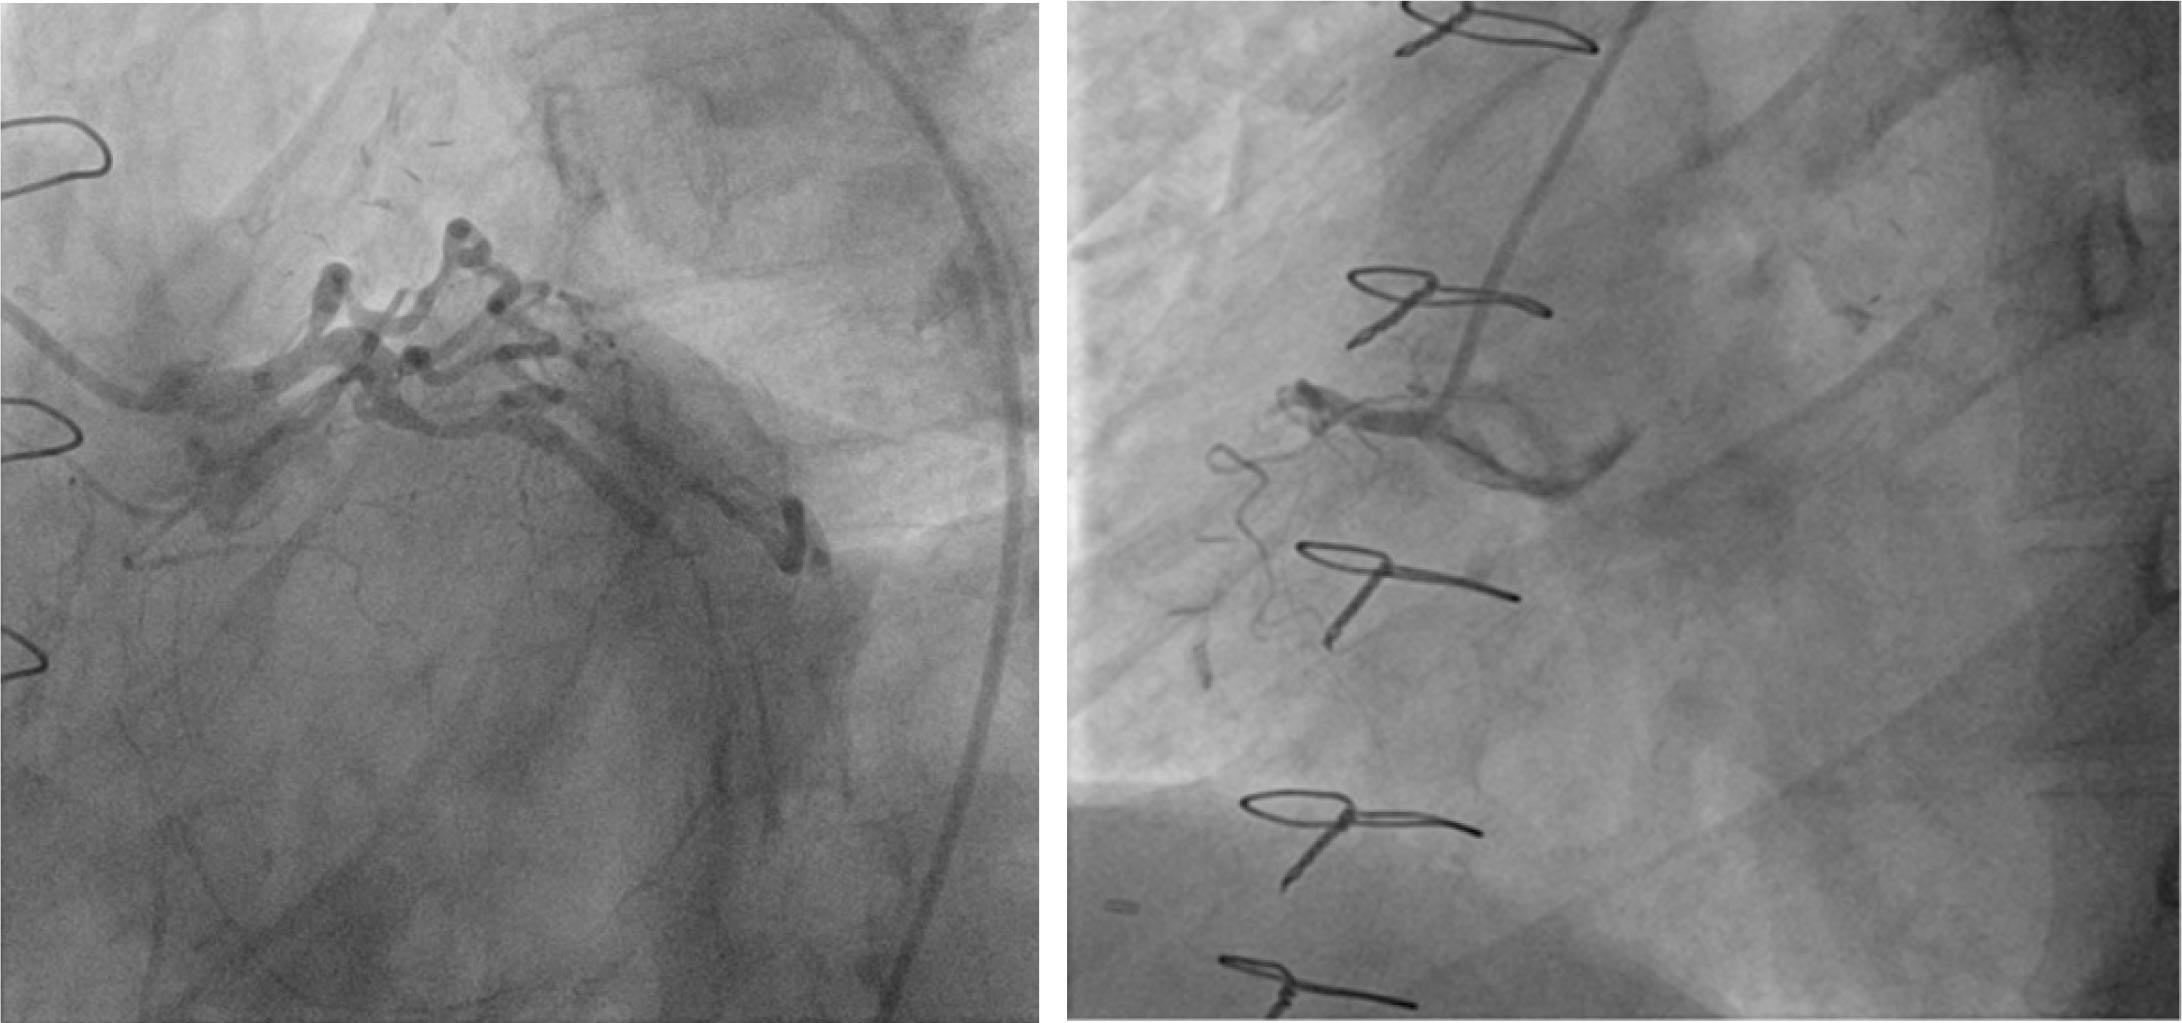

He was taken immediately to the catheterization laboratory. Transfemoral diagnostic coronary angiography using CORDIS DIAGNOSTIC 6F JL4 (IndiaMART) and JR4 (Oscor’s Angios) catheters revealed patency of LAD graft, significant stenosis of the proximal left circumflex coronary artery (LCX) followed by chronic total occlusion of the distal segment, and complete thrombotic occlusion of the proximal right coronary artery (RCA) with retrograde filling of distal RCA through collaterals from LAD (Figure 1). Consequently, we proceeded to PCI to the proximal RCA. We used a CORDIS DIAGNOSTIC 6F JL4 (IndiaMART) guide catheter to engage the RCA, and an attempt was made to cross the culprit lesion with a 0.014” PT2 moderate support guidewire (Boston Scientific). The control contrast injection revealed a long spiral dissection of RCA (Type D according to the NHLBI classification) starting fromthe tip of the guide catheter with antegrade extension to the distal segment and evidence of thrombus in the mid-portion and slow flow. Subsequent angiogram revealed retrograde extension into the right aortic sinus of Valsalva and ascending aorta and dye retention extending more than 50 mm in the aortic wall, consistent with class III Dunning aortocoronary dissection (Figure 2).

LAO caudal view of selective left coronary angiography. Critical stenosis of ostial and mid LAD, significant stenosis of proximal LCX, chronic total occlusion of distal LCX. Retrograde filling of distal RCA through collaterals from LAD (arrow). LAO view: complete thrombotic occlusion of proximal RCA.